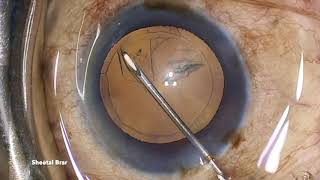

CCC capsulorhexis done with a cystotome How to create the perfect Cystitome to achieve the perfect capsulorrhexis - Finer Points.

How to create the perfect Cystitome to achieve the perfect capsulorrhexis - Finer Points. Continuous circular capsulorhhexis with a needle

CCC capsulorhexis done with a cystotome How to create the perfect Cystitome to achieve the perfect capsulorrhexis - Finer Points.

How to create the perfect Cystitome to achieve the perfect capsulorrhexis - Finer Points. Continuous circular capsulorhhexis with a needle